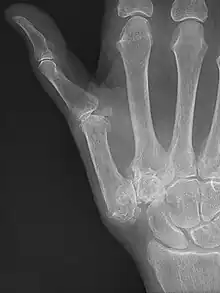

Joint Replacement

X-ray of trapeziometacarpal joint replacement. Left hand of a 58-year-old woman.

The joint can be replaced with artificial material. An artificial joint is also referred to as a prosthesis. Prostheses are more problematic at the trapeziometacarpal joint compared joints like the knee or the hips.

[27]Prostheses come in many varieties, such as spacers or resurfacing prostheses.

It’s not clear within the current literature that a prosthesis has any advantage over trapeziectomy.[27]

Overall, joint replacements are related to long-term complications such as subluxation, fractures, synovitis (due to the material used) and nerve damaging.[35] In many cases revision surgery is needed to either remove or repair the prosthesis. Also note that usage of a joint replacement is heavy in costs.

The quality of the prostheses is improving and there is reason to believe this will have a positive effect on outcome in the years to follow.[27]